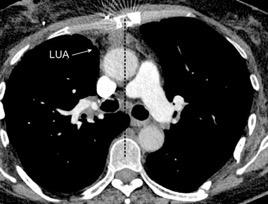

Parálisis frénica transitoria tras cirugía de válvula aórtica

Parálisis frénica transitoria post cirugía cardiaca (10%).

Puede acompañarse de atelectasia del LII.

Benjamin JJ et al. . Left lower lobe atelectasis and consolidation following cardiac surgery: the effect of topical cooling on the phrenic nerve. Radiology 1982